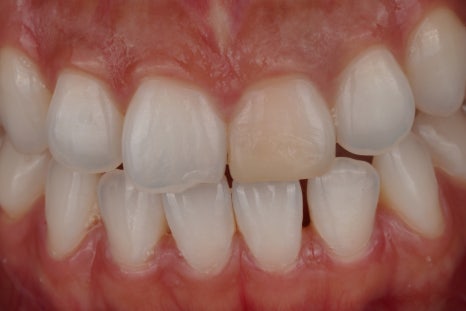

신경치료가 완료된 모습

먼저 신경치료가 되어 있는 치아를 열어서 안쪽 상태를 확인하는 과정을 거쳐요.

1주 뒤

그리고 변색의 원인이 될 수 있는 신경관 입구 쪽의 약재나 충전물을 정리해 줍니다.

이 과정만으로도 색이 조금 밝아질 때도 있어요.

2주 뒤

그다음에는 치아 내부 공간에 미백 약제를 넣어서 일정 시간 작용하도록 하는데요. 이 약제에서 산소가 발생하며 조금씩 밝게 만들어 주는 원리에요^^

3주 뒤

치아 상태에 따라 한 번으로 끝나는 경우도 있지만 보통은 몇 차례 반복하면서 주변 인접치와 자연스럽게 어울리는 색을 맞춰 가고 있어요.

산소가 빠지려면 충분한 시간을 기다리는 것이 중요하거든요.

완료 후

한 2주 정도 기다리면 이렇게 건강한 자연치와 같은 모습으로 바뀌게 된답니다^^